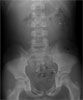

An abdominal radiograph (Figure 1) revealed multiple radiopaque specks throughout the colon and moderate stool retention. The patient was hospitalized for bowel clean-out and initiation of chelation therapy with succimer (meso-2,3- dimercaptosuccinic acid [DMSA]). Inspection of his stool revealed parts of refrigerator magnets, string, paper, labels, pigments of various colors, pencil points, and other unidentifiable particles (Figure 2). The exact source of lead was not determined- even after an extensive environmental inspection.